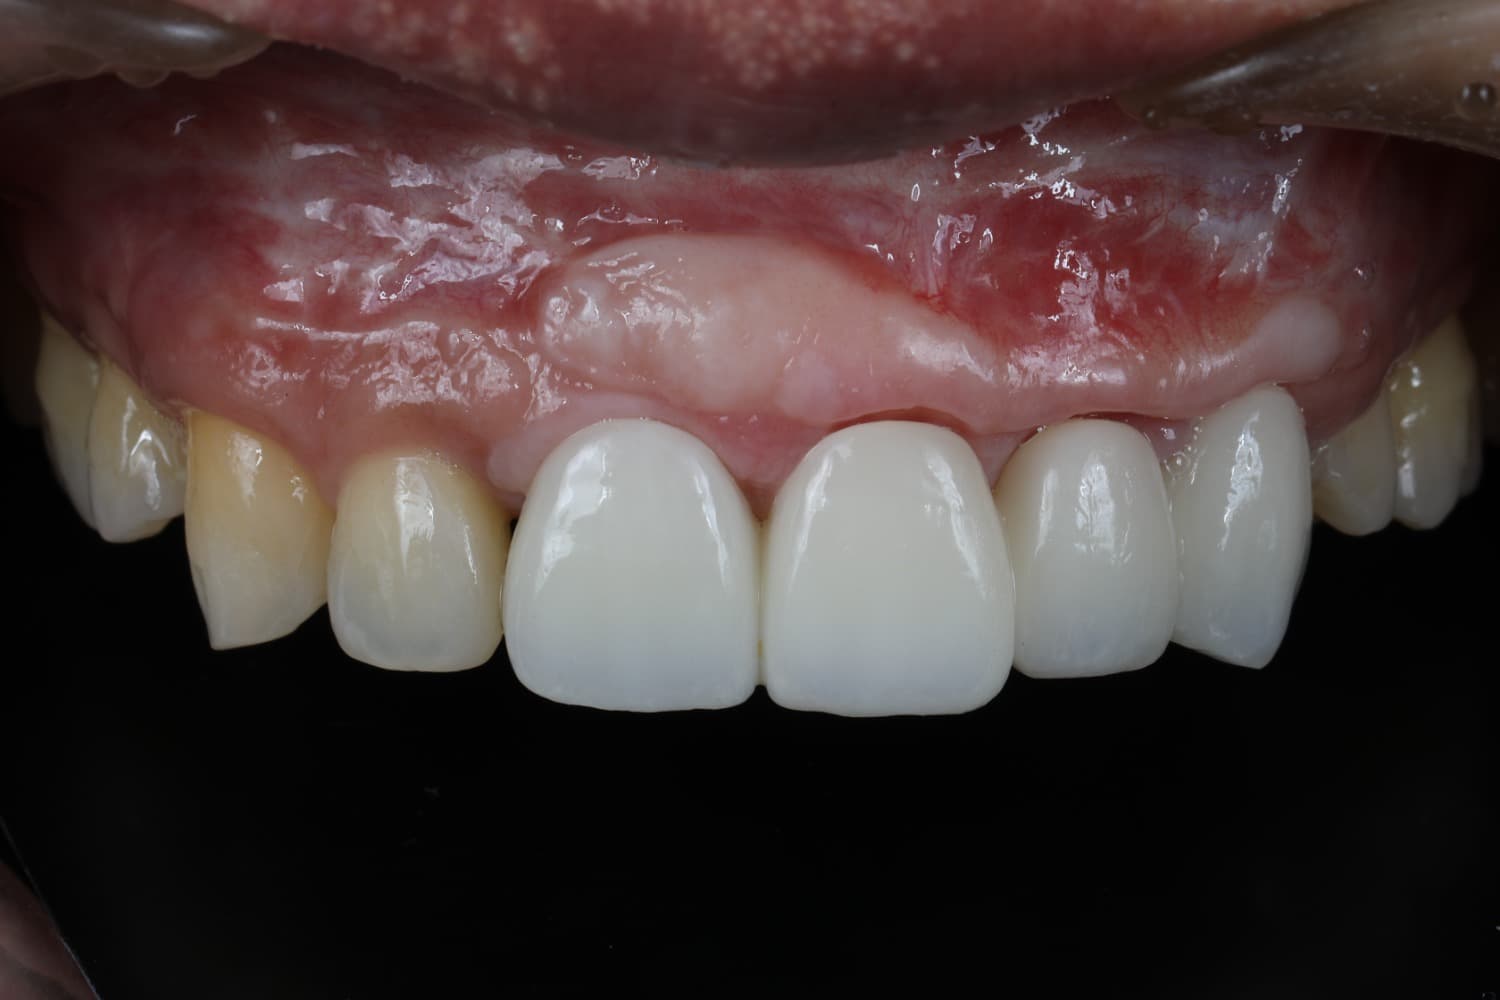

連続欠損に対するインプラント治療

Before

After

喪失した連続欠損に対してインプラントGBRCTGを行い、審美的・機能的に回復を行なった

年齢

30代

性別

男性

主訴

前歯の入れ歯を避けたいのでインプラントをしてほしい

治療期間

2年

治療回数

20回

費用

200万円

副作用・リスク

腫脹、疼痛